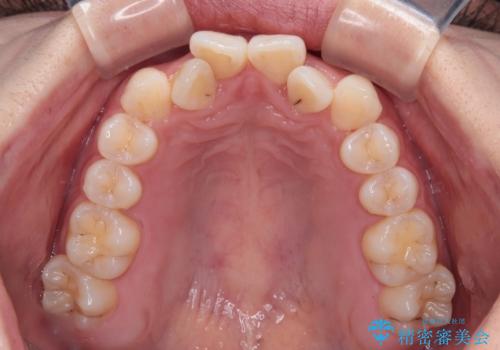

前歯のクロスバイト 裏側に隠れた歯をワイヤー装置で短期間治療

- 上顎前歯のクロスバイトを気にして来院された患者様です。

装置の外見を気にしていましたが、短期間で治療を終えることができるだろうと伝えると、安価であるメタルブラケットを選択されました。

想定通り、1年強で綺麗に仕上げることができました。